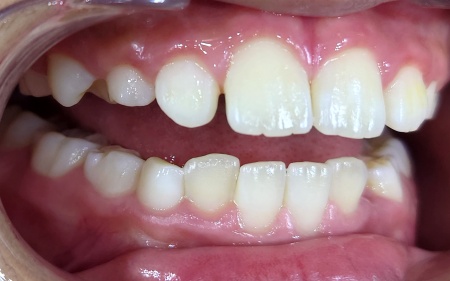

インプラントがあごの骨にしっかりと定着したことを確認してから、型取りを行いインプラントの上に取り付ける人工歯を作製します。

人工歯の種類は治療部位が笑った際に目立つ場所であったため、自然な見た目で強度もあるセラミック製のジルコニアクラウンを選択しました。

その後、完成したジルコニアクラウンを歯茎から自然に生えているように見せるため形や取り付け位置を工夫して装着し、治療を終了しました。